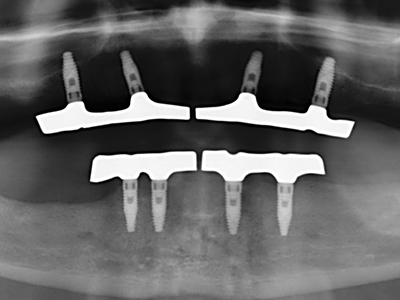

Piezo surgery has additional advantages when harvesting bone blocks. In addition to the high precision with osteotomy described above, the use of the thin saw tips specifically minimizes loss of material. Greater loss of material during harvesting can be expected with the thicker instrument tips, particularly when using Lindemann drills (Lakshmiganthan, Gokulanathan et al. 2012). The basal separation, which is necessary particularly for retromolar block transplants, is simplified by specially designed rectangular saws, with the result that piezo surgery is viewed as a precise, simple and safe procedure for harvesting retromolar bone blocks (Happe 2007) (Fig. 1-12).

Indication: Bone splitting

Bone tissue is not simply a mineral structure but also contains a substantial proportion of collagen fibres. This means it not only has good compressive strength but also a degree of flexibility, which can be taken advantage of when performing bone augmentations. In the classical expansion procedure using bone splitting, the atrophied alveolar ridge is split longitudinally and carefully expanded after reaching an adequate osteotomy depth (Fig. 13-16), ideally without substantial removal of the periosteum (Brugnami, Caiazzo et al. 2014, Stricker, Fleiner et al. 2014). Screw and plate systems with increasing expansion distance have proven effective in separating the two bone lamellae while remaining below the fracture threshold. In general, residual bone widths of at least 3–4 mm are required (Chiapasco, Zaniboni et al. 2006) to guarantee adequate flexibility and sufficient bone coverage of the future implants. If necessary, a vertical relief osteotomy on one or both sides can improve flexibility. A combination with additional augmentation techniques, particularly on the buccal side, has been described as an alternative to the classical technique.

The splitting procedure is particularly atraumatic and there is no significant loss of dimension when using piezosaws, and there are no significant differences between implants in split jaws and implants in an alveolar ridge without a bone deficit (Chiapasco, Zaniboni et al. 2006, Danza, Guidi et al. 2009). However, sufficient continuous irrigation is essential, particularly with locally restricted and deep splitting to prevent thermal stress in the apical osteotomy regions.